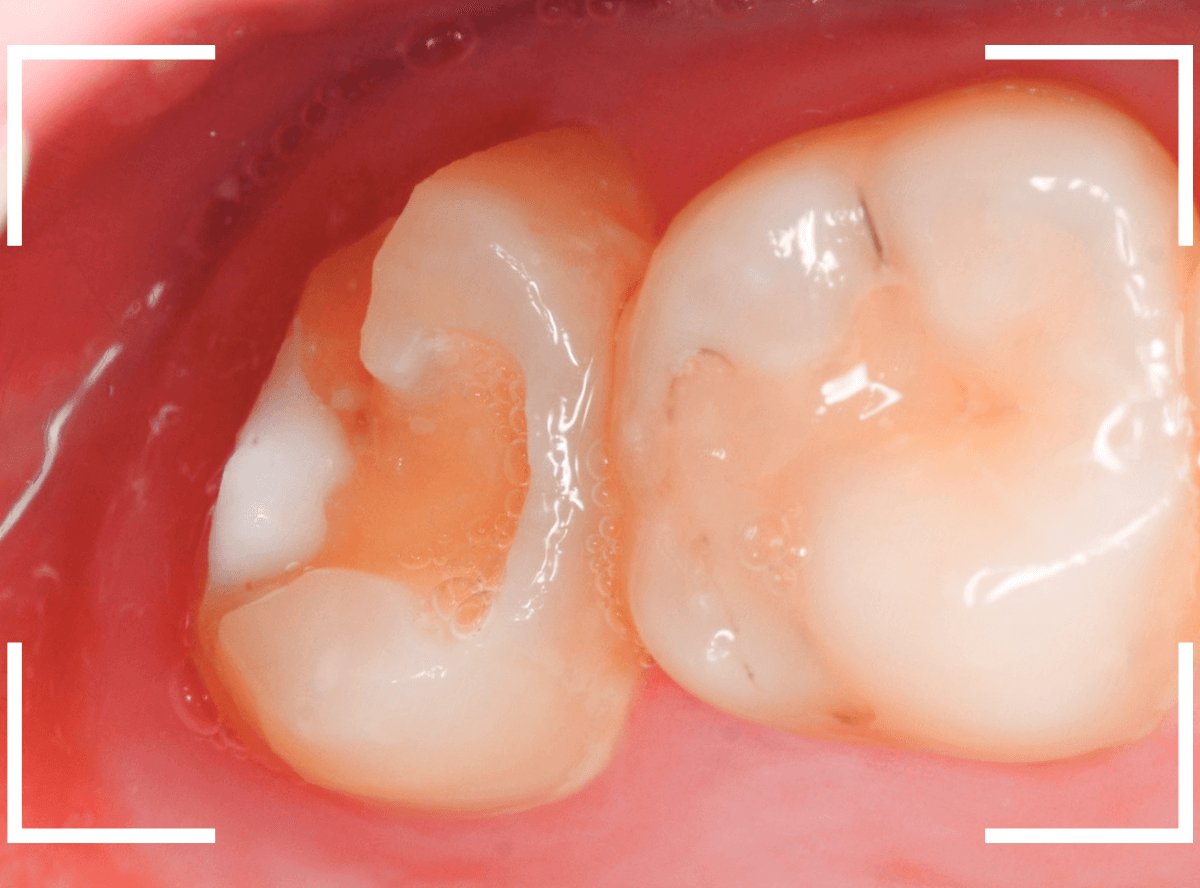

Case.8 治療を中断して、つめものが取れてさらに虫歯が進行したケース

こちらも、前のケースの方と同じように、治療中断後、つめものが取れて長期間放置してしまった患者さんのケースです。

しみるなどの症状が現れたので、来院に至ったようなのですが、症状が出ている場合、だいたい、虫歯は重症化している事が多いです。

レントゲン写真で確認します。

青いラインが神経、赤いラインが虫歯と思われる部分です。

前後の歯まで、虫歯が広く進行しているのが想定できます。

虫歯の治療を開始すると、すぐに深めの虫歯が出てきました。

神経に近い部分まで虫歯が進行していますので、慎重に虫歯を除去します。

全ての虫歯を除去しました。

前後の歯にまで虫歯が広く進行していました。

場合によってはお痛みが出る可能性をお話しし、お薬をつめて経過観察をしました。

いつものフレーズになりますが、症状が出てからの歯科受診は、このように大きく歯を削る治療になります。また、手遅れになっている事も多いです。